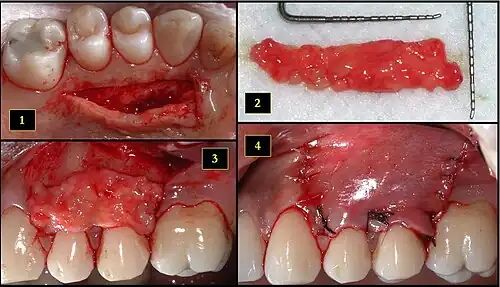

- Ipsilateral palatal mucosa serving as the donor site

- The retrieved connective tissue, approximately 25 × 6 mm in dimension

- Connective tissue placed at recipient site

- Recipient site flap coronally advanced and sutured to entirely cover the graft